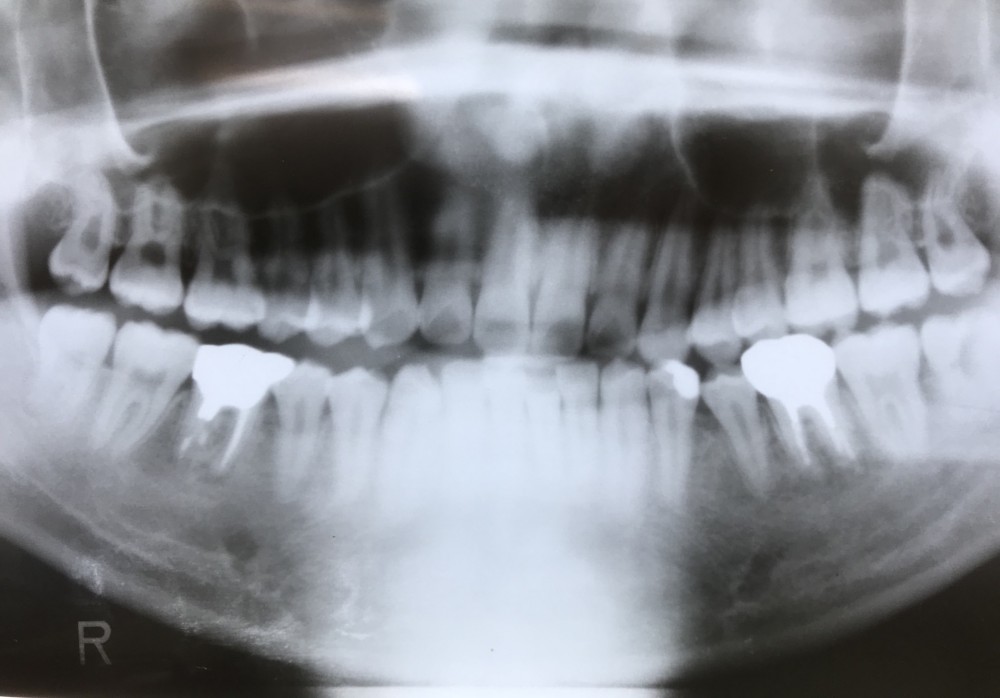

下は初診時の写真です。

下左右6の感染根管、及び左下Eの感染根管が疑われます。

右下6の遠心ポケットは根尖病変と交通。

抜歯の可能性もありますが、年齢を考えると、まずは根管治療を行なって、治癒力に期待したいところです。